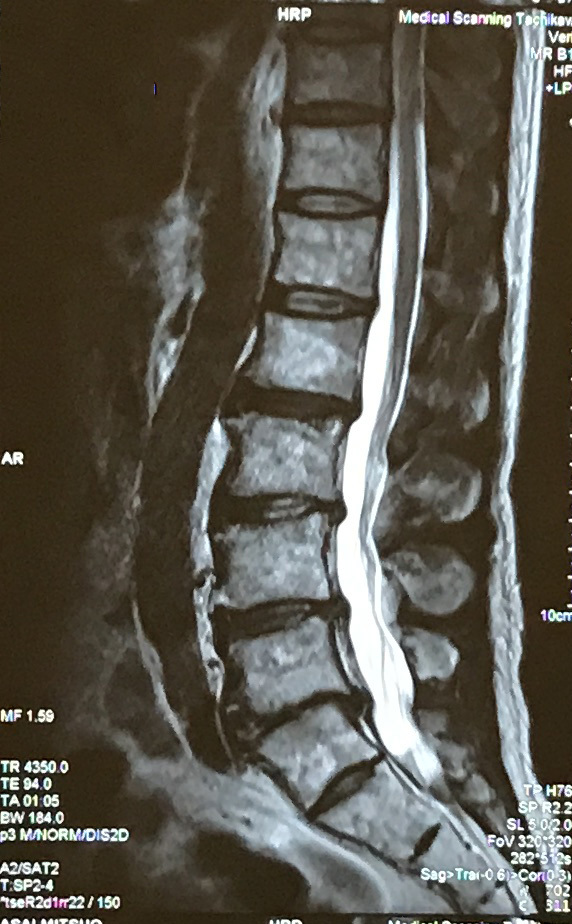

12/2(月)の朝から、足の甲の痺れ、足首の背屈の障害が突然発生しましました。症状から典型的な「腓骨神経障害」です。膝の横の腓骨の上を走る神経は筋肉に隠されていないため、物理的につぶされて傷つきやすいそうです。酔っぱらって寝て、何かに足をこすりつけたまま、寝ちゃったんじゃないかと言われました。しかし、痺れがでる前夜に腰がうずく痛みを感じたのと、この症状は、腰椎側の可能性も排除できないので、MRIも撮ってきました。MRI画像結果を見る限りは、ヘルニアの傾向はありませんでした。また、腰部脊柱管狭窄症と言われる脊柱への圧迫も見られませんでした。ただ、第5腰椎の背骨間が狭く、腰椎側の可能性はないとは言い切れないようでした。所謂、神経回復ビタミンを飲みつつ様子をみる保存的治療中です。

〇 MRI画像

・MRIだと神経網が写るんですね。

・MRIは被爆しなくていいです。今年は、CTとかシンチグラフィーでは、放射性同位体を注射されてるますからねぇ。